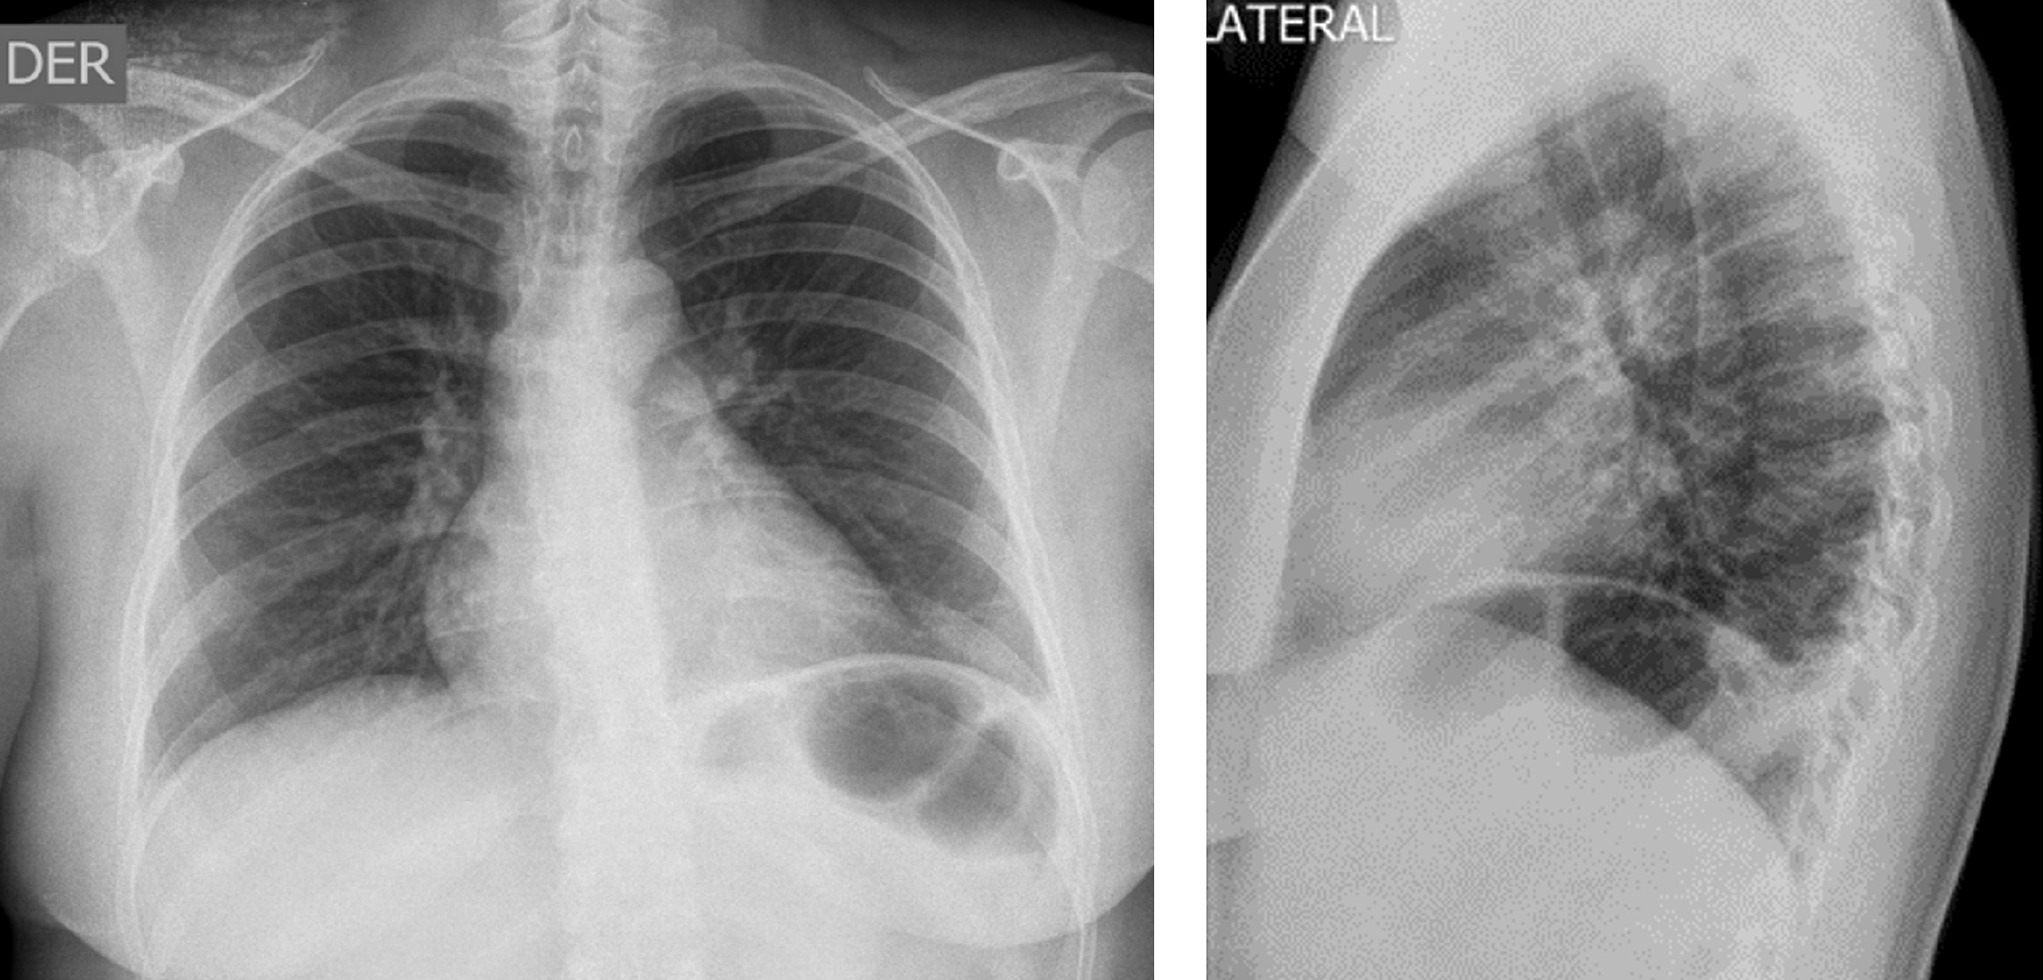

Caso clínico: es una mujer de 39 años que ingresó con un cuadro clínico de 12 horas de evolución consistente en dolor en zona torácica izquierda irradiado a la región escapular ipsilateral que se exacerba con la respiración y los cambios de posición, refirió un antecedente de trombosis venosa profunda en la pierna derecha. Los paraclínicos indicaron anemia microcítica hipocrómica y trombocitosis con imagen sugestiva de infarto pulmonar, angio-TAC con trombo a nivel del ramo segmentario lobar inferior derecho, derrame pleural derecho y atelectasia. Se indicó el estudio de anemia con colonoscopia, que reportó una pancolitis ulcerativa en fase aguda con escaso sangrado, y perfil inmunológico resultó negativo. Se inició el manejo con anticoagulante más mesalazina y metilprednisolona.